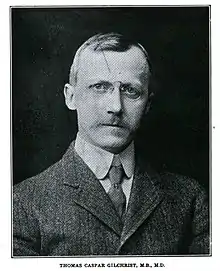

Blastomycosis has existed for millions of years but was first described by Thomas Caspar Gilchrist in 1894. Because of this, it is sometimes called "Gilchrist's disease".[17]

Blastomycosis was first described by Thomas Caspar Gilchrist in 1894, as a skin disease. Because of this, blastomycosis is sometimes called "Gilchrist's disease".[17] Gilchrist initially identified the cause of the disease as a protozoan, but later correctly identified it as a fungus.[73] In 1898 he and William Royal Stokes published the first description of Blastomyces dermatitidis.[73] Gilchrist referred to the disease as "blastomycetic dermatitis".

The systemic spread of blastomycosis was first described in 1902, in a case that had been misdiagnosed as a combination of tuberculosis and a blastomycosis skin infection. In 1907, the dimorphic nature of the Blastomyces fungus was first identified.[73] In 1912, the first case of canine blastomycosis was reported.[15]

Prior to the 1930s, blastomycosis was not clearly distinguished from similar fungal conditions.[73] A paper by Rhoda Williams Benham in 1934 distinguished the causative agent of blastomycosis from cryptococcosis and coccidioidomycosis.[73]